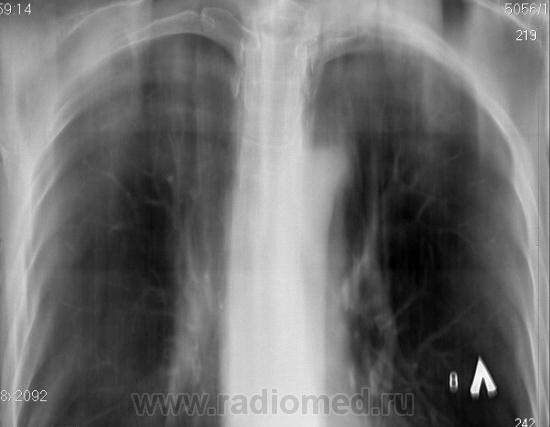

Для начала, неплохо бы R- граммы посмотреть, тогда будет понятна цель выполнения томографии.

По томограммам не понятно что хотели получить? Интересовали эти маленькие плотные очаги?

Справа на верхушке инфильтративная тень. Слева в задних отделах мелкие буллы.

На последнем срезе тень в 1 сегменте, мелкие полости в верхних долях с обеих сторон.